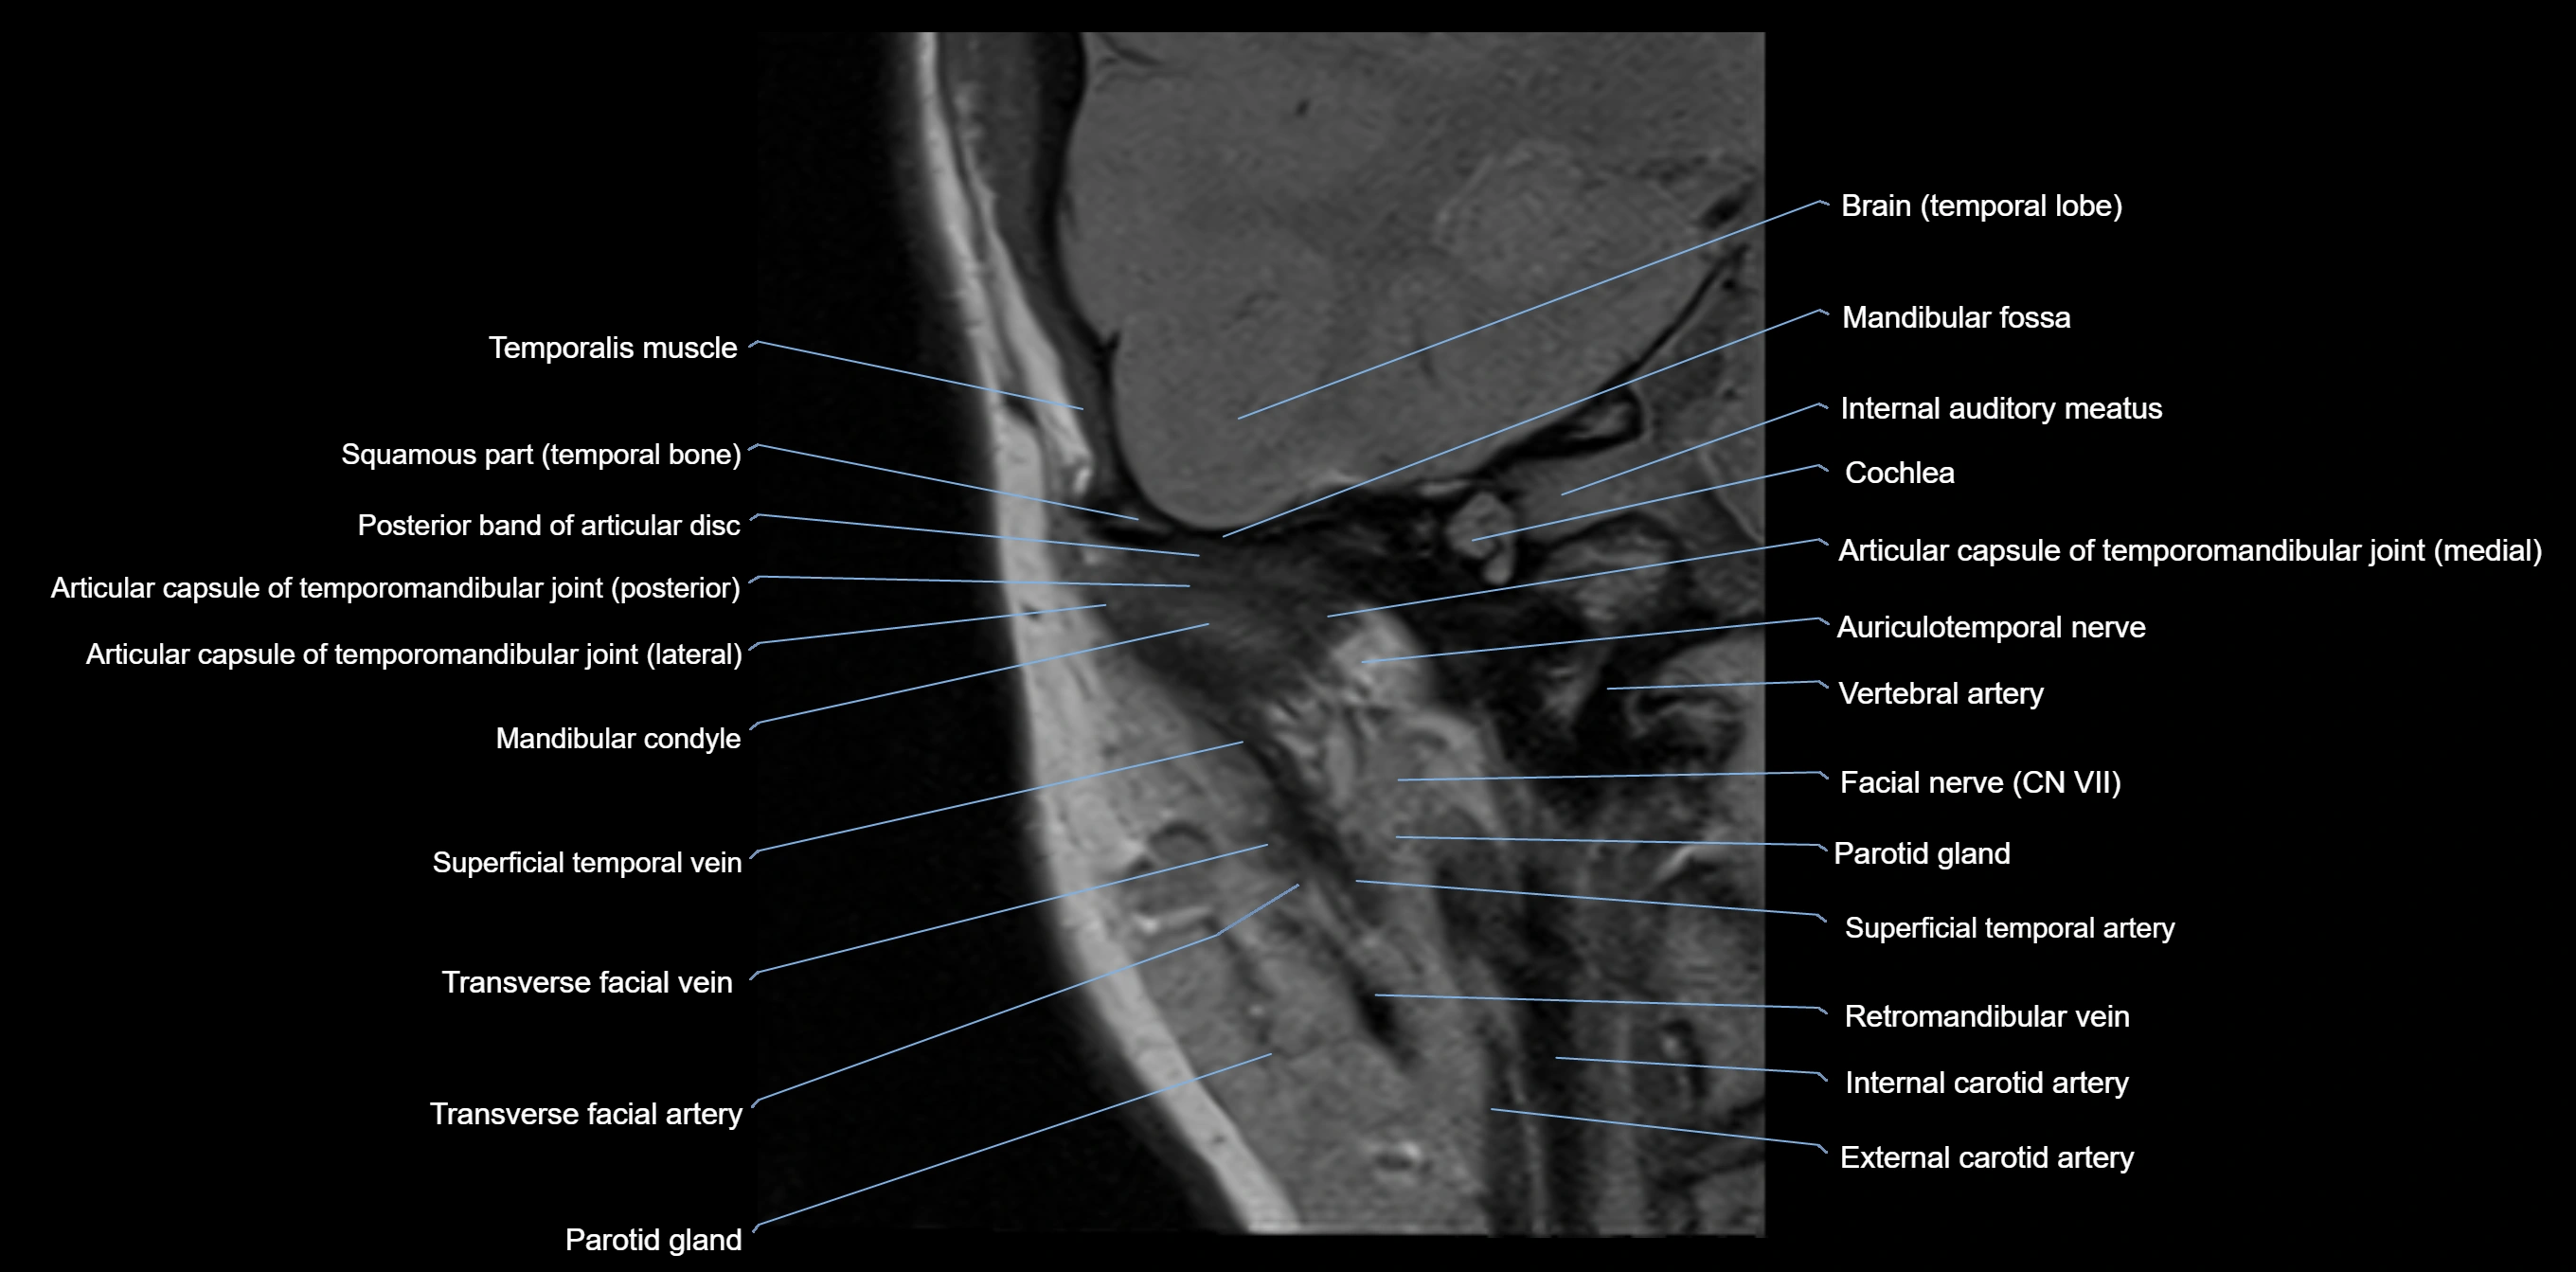

MRI appearance

T1-weighted images:

• Cortical bone: Low signal intensity

• Cancellous marrow: Intermediate to high signal depending on fatty content

• Teeth: Signal void structures

• Adjacent soft tissues: Normal gingiva and oral mucosa signal

T2-weighted images:

• Cortical bone and teeth: Low signal

• Marrow: Intermediate signal